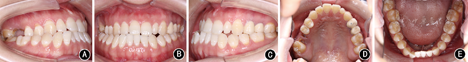

患者女性,23岁。主诉:"地包天",面部不对称,要求改善面型。7年前曾于外院行正畸治疗1.5年,后随生长复发;否认家族史。

患者正面观不对称,颏部右偏4.0 mm,面下1/3过长。侧面凹面型,上颌轻度后缩,下颌前突。口内检查:

残根,右侧磨牙近中关系,左侧完全近中关系;前牙浅覆

、浅覆盖;上牙列无拥挤,下牙列拥挤2.0 mm。上中线正,下中线右偏5.4 mm。

过小牙,

烤瓷联冠,

颊向倾斜,

舌向倾斜。X线检查示上颌后缩,下颌前突伴偏斜。头影测量显示上颌突度的SNA角73.82°,下颌突度的SNB角76.64°,上下颌相对位置的ANB角-2.82°,L1/MP角(下中切牙与下颌平面所成角度)64.95°。

安氏Ⅲ类错

畸形,毛氏Ⅱ1;骨性Ⅲ类,上颌后缩下颌前突伴偏斜。

像;B:正面

像;C:左侧

像;D:上颌

面像;E:下颌

面像